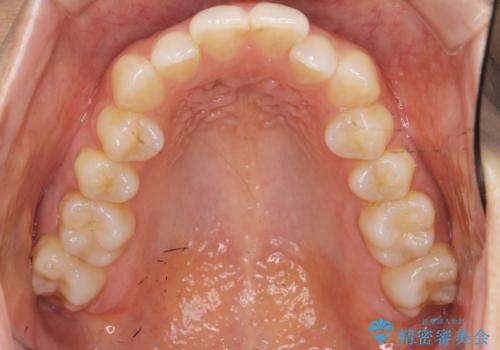

前歯のガタつきをマウスピースで治したい!

- 気になる前歯のガタつきをマウスピースで治療したいと希望され来院されました。

当日に矯正検査を行い、骨格・歯に問題がないことを確認しマウスピースによる矯正治療を進めます。

IPRを前歯部に少量行うことで、非抜歯でも前歯が外に飛び出さない仕上がりを達成できました。